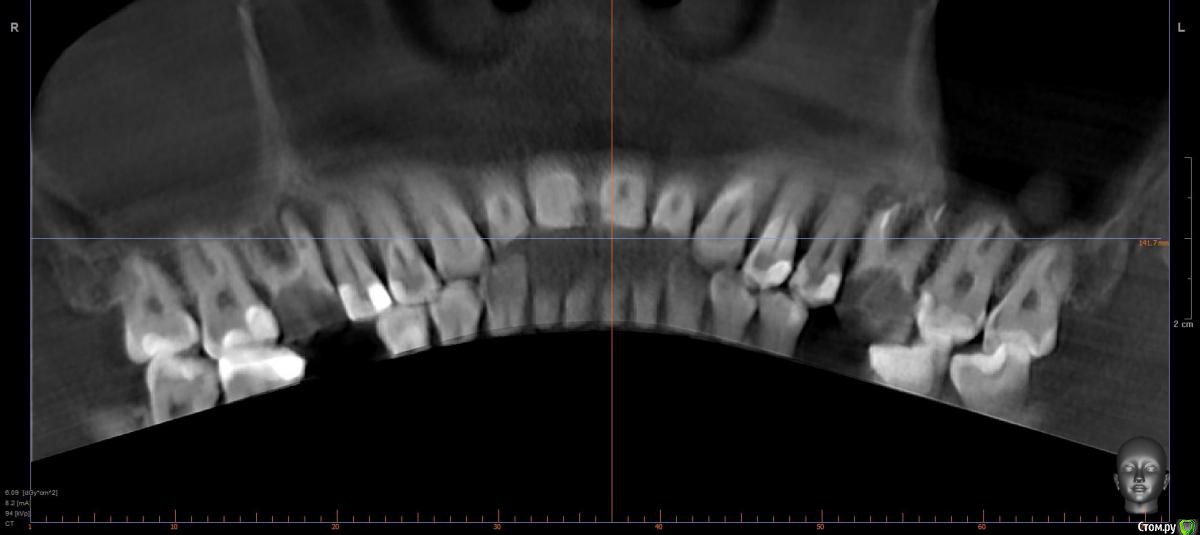

Faramir Опубликовано 18 апреля, 2019 Поделиться Опубликовано 18 апреля, 2019 (изменено) Сделал КТ. По 3D виду появился вопрос. Что это за разряжение кости в области шестерок на 3D виде КТ? Это нормально для КТ в этом месте или идет патологический процесс? Также интересно восстановится ли тут кость после удаления или лечения? Над левой шестеркой есть свищ над которым периодически вырастает и лопается белый шарик. Десна у правой шестерки за месяц дважды воспалялась, появлялась припухлость в виде валика, но после полосканий в течении 3 дней проходила. Можно ли спасти эти шестерки перелечив каналы или нужно удалять? У них в корнях стекловолоконные штифты на которые приклеены коронки/накладки наверное из керамики. Заранее спасибо за ответы. Изменено 18 апреля, 2019 пользователем Faramir Ссылка на комментарий